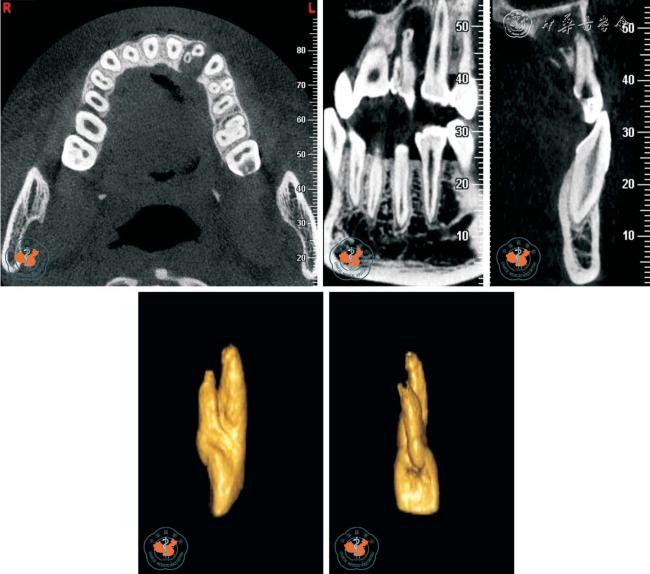

2. 观察牙根吸收情况:Tronstad12根据牙根吸收的起源部位将牙根吸收分为内吸收和外吸收,外吸收又根据不同临床表现分为炎症性外吸收、牙颈部外吸收和替代性外吸收。 早期牙根外吸收多无临床症状,X 线检查时才能发现。 由于根尖片只能显示相互重叠的二维影像,因此常不能清晰的显示吸收范围,难以准确评估牙根吸收的严重程度。 Estrela 等13报道指出根尖片识别牙根外吸收的假阴性率约为51.9%,假阳性率约为15.3%,尤其当病损位于颊侧或舌侧根面时,准确率更低。 而且,传统根尖片不能发现小于直径0.6 mm、深度0.3 mm的缺损。 CBCT 在很大程度上弥补了根尖片的缺点,其多层面重建(multiplannar reconstruction,MPR)技术可以显示病变的真实形态和部位,确定病变范围、破坏程度及周围牙槽骨的吸收状况,并可发现先前未发现的吸收缺损,有助于确定牙根吸收后的治疗规划,提高了患牙保存率(图3 ~4)。

图3 CBCT 轴位及MPR 重建显示上颌左、右第一磨牙牛牙症,其中左侧上颌第一磨牙根尖内吸收伴颊侧根折

图4 CBCT 轴位、VR、CPR 及MPR 重建冠、矢状位图像清晰显示根牙周病致牙根外吸收